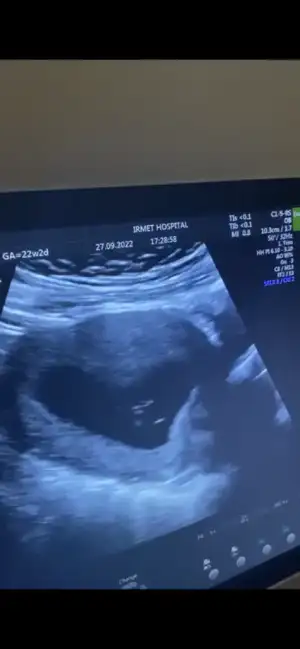

Canım ultrasonda niye 22 hafta 2 günlük yazıyor yanlış mı yazılmışBebişe nub a göre yorum yapabilecek var mı kızlarr aşırı merak ediyorum B BarbieveKen göreveebirde kalp atışı dk da 144 dedi araştırmalarıma göre 140 ın üstü kız yazıyor

ay öyle güzel oynuyordu ki pıtır pıtırdı eller ayakları